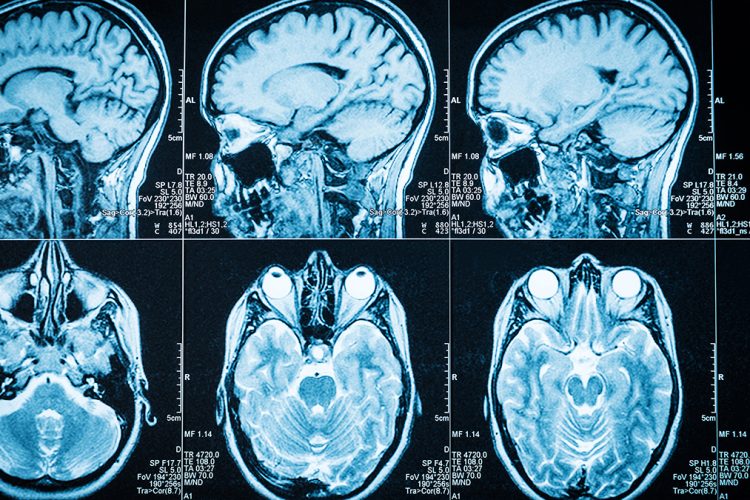

UBT newsNë nivel global, Organizata Botërore e Shëndetësisë (OBSH) vlerëson se epilepsia prek rreth 50 milionë njerëz.

Nga këto, rreth 80% jetojnë në vende me të ardhura të ulëta ose të mesme.

Simptoma kryesore për shumicën e njerëzve me epilepsi janë konvulsionet, që shkaktohen nga rritja e aktivitetit elektrik në tru.

Ato janë dridhje të pakontrolluara të trupit, si pasjoë e kontraktime të muskujve dhe qetësimit të tyre në mënyrë të përsëritur.